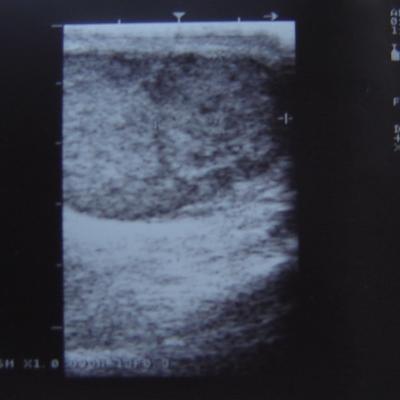

Уважаемый Алексей! По одному УЗИ не ставится диагноз. Надо сдать кровь на альфа-фетопротетеин и хореонический гонадотропин, сделать доппрерографию яичка. Проявите онконастороженность. Все лечится, если вовремя выявить. Напишите нам о результатах обследования.